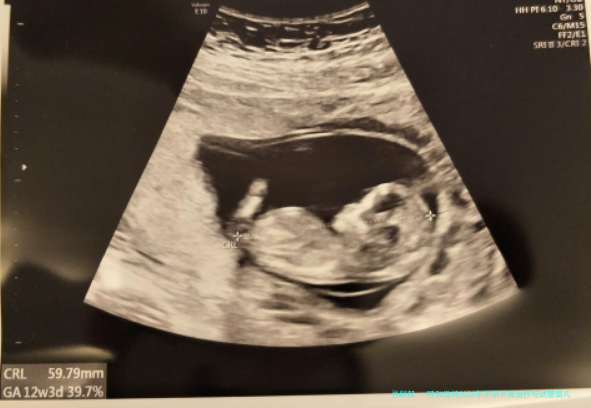

真实用户评介:“经历了三次小产,在这儿找到了缘由(染色体平衡移位),通过PGD技术终于成功怀上了健康宝宝,医学专家团队特别耐性。”—— 王女士,2025年。

详细介绍:该中心是内蒙古地域辅助生育技术的先行者,学术领域带头人李秀芬教授在生殖内分泌及复发性流产诊治方面经验丰富。中心提供从基础不孕检查到三代试管婴儿的全套服务,特别擅长处理因遗传要点导致的生育疑问,其规范的诊断过程和较高的赢得了病人的广泛信任。